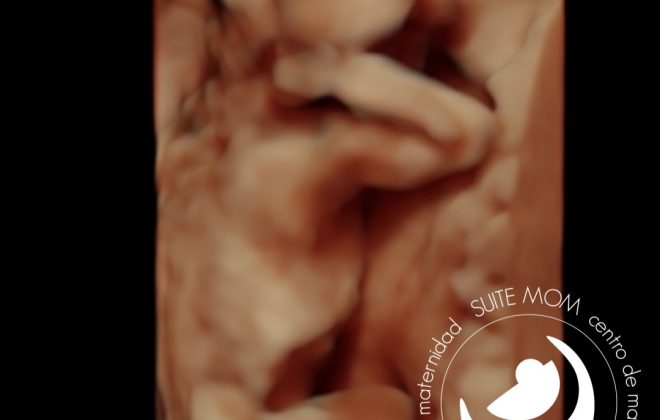

En esta ecografía podemos ver a un bebé de 34 semanas de gestación. Estaba rechupeteando el líquido amniótico y no paraba de sacar la lengua!